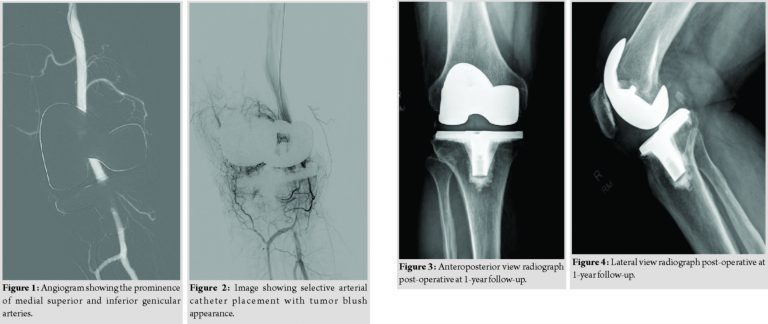

In consultation with vascular surgeons and interventional radiology, he underwent a computed tomography angiogram to evaluate for any vascular abnormalities, leading to hemarthrosis of the knee. This demonstrated prominence of medial superior and inferior geniculate vessels in the right knee, but a detailed evaluation was limited due to artifacts form the knee implant. No extravasation was identified. He then underwent a right femoral angiography through the left femoral approach which again demonstrated prominent medial superior and inferior geniculate arteries (Fig. 1). A 5 Fr angiography catheter was placed in the right medial superior geniculate artery and a 3 Fr. Microcatheter was placed coaxially throughthe 5 Fr catheter more distally into the medial superior geniculate artery for super selective angiography, which showed synovial hypervascularity and blush. This geniculate artery was subsequently embolized with one-fourth vial of microspheres (500 µ in size). The 5 Fr angiography catheter was then placed in the right medial inferior geniculate artery and a 3 Fr microcatheter was placed coaxially via the 5 Fr catheter more distally into the medial inferior geniculate artery for superselective angiography, which showed synovial hypervascularity and tumor blush (Fig. 2). This geniculate artery was subsequently embolized with one-fifth vial of microspheres (500 micron in size). Post-embolization right femoral angiography showed these geniculate arteries to be occluded. The patient was discharged home on the same day and was recommended to return to activities as tolerated. He was seen in the orthopedic clinic at 1 month from the procedure at which time, the patient reported complete resolution of the swelling and pain in his right knee. He was back to all his activities with no limitations. The patient continues to be asymptomatic and no recurrence of the hemarthrosis at 12-month follow-up (Fig. 3and 4).

Recurrent spontaneous hemarthrosis can severely limit the function of the knee following a total knee arthroplasty. It should be promptly diagnosed, and a course of conservative treatment should always be tried before any surgical procedures. Saksena et al. [9] recommended an algorithmic approach in the evaluation of hemarthrosis of the knee. All the anticoagulation medications should be stopped, and the patient should be evaluated for any coagulopathies. Rest, ice, aspiration, and immobilization should be done following a large hemarthrosis. Prosthetic joint infection should always be ruled out with inflammatory markers and cultures of the aspirate [9,10]. When the conservative treatment method fails, and the patient has recurrent hemarthrosis, angiography has been used as a first-line procedure to help with the diagnosis and then proceed with treatment [9]. This technique has been successfully used in the treatment of pseudoaneurysms and arteriovenous fistulas previously [11,12]. Many authors have been using selective arterial embolization of the geniculate arteries to diminish the blood flow into hypertrophic synovium, thereby treating the recurrent hemarthrosis. Weidner et al. [10] reported successful resolution of recurrent hemarthrosis in 12 of 13 patients treated with geniculate arterial embolization. One clinical failure likely represented misdiagnosed prosthetic joint infection. Two patients had transient cutaneous ischemia following embolization which resolved spontaneously. In their study, the average time interval between arthroplasty and onset of hemarthrosis was 47 months. Bagla et al. [6] treated fivepatients with selective geniculate arterial embolization; angiography demonstrated synovial hypervascularity with geniculate artery tumor blush appearance in all patients. There was a complete resolution of the symptoms and effusion at an average time of 2.6 weeks with no recurrences during the follow-up. The angiographic examination in our patient also demonstrated typical synovial hypervascularity with the geniculate artery tumor blush appearance. It was successfully treated with microsphere embolization of the geniculate artery.